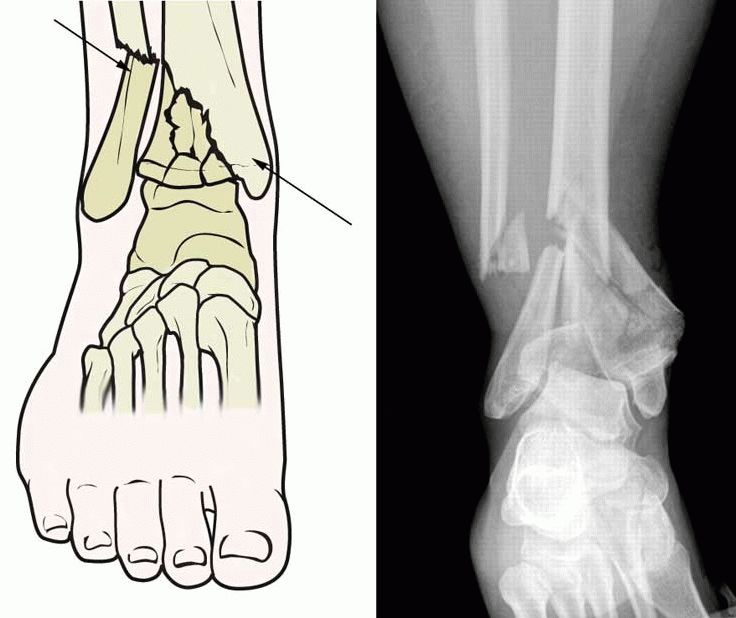

- Оскольчатые — края сломанных костей неровные, с зазубринами и различными формами.

- Со смещением — концы отломков находятся на значительном расстоянии друг от друга и их трудно совместить.